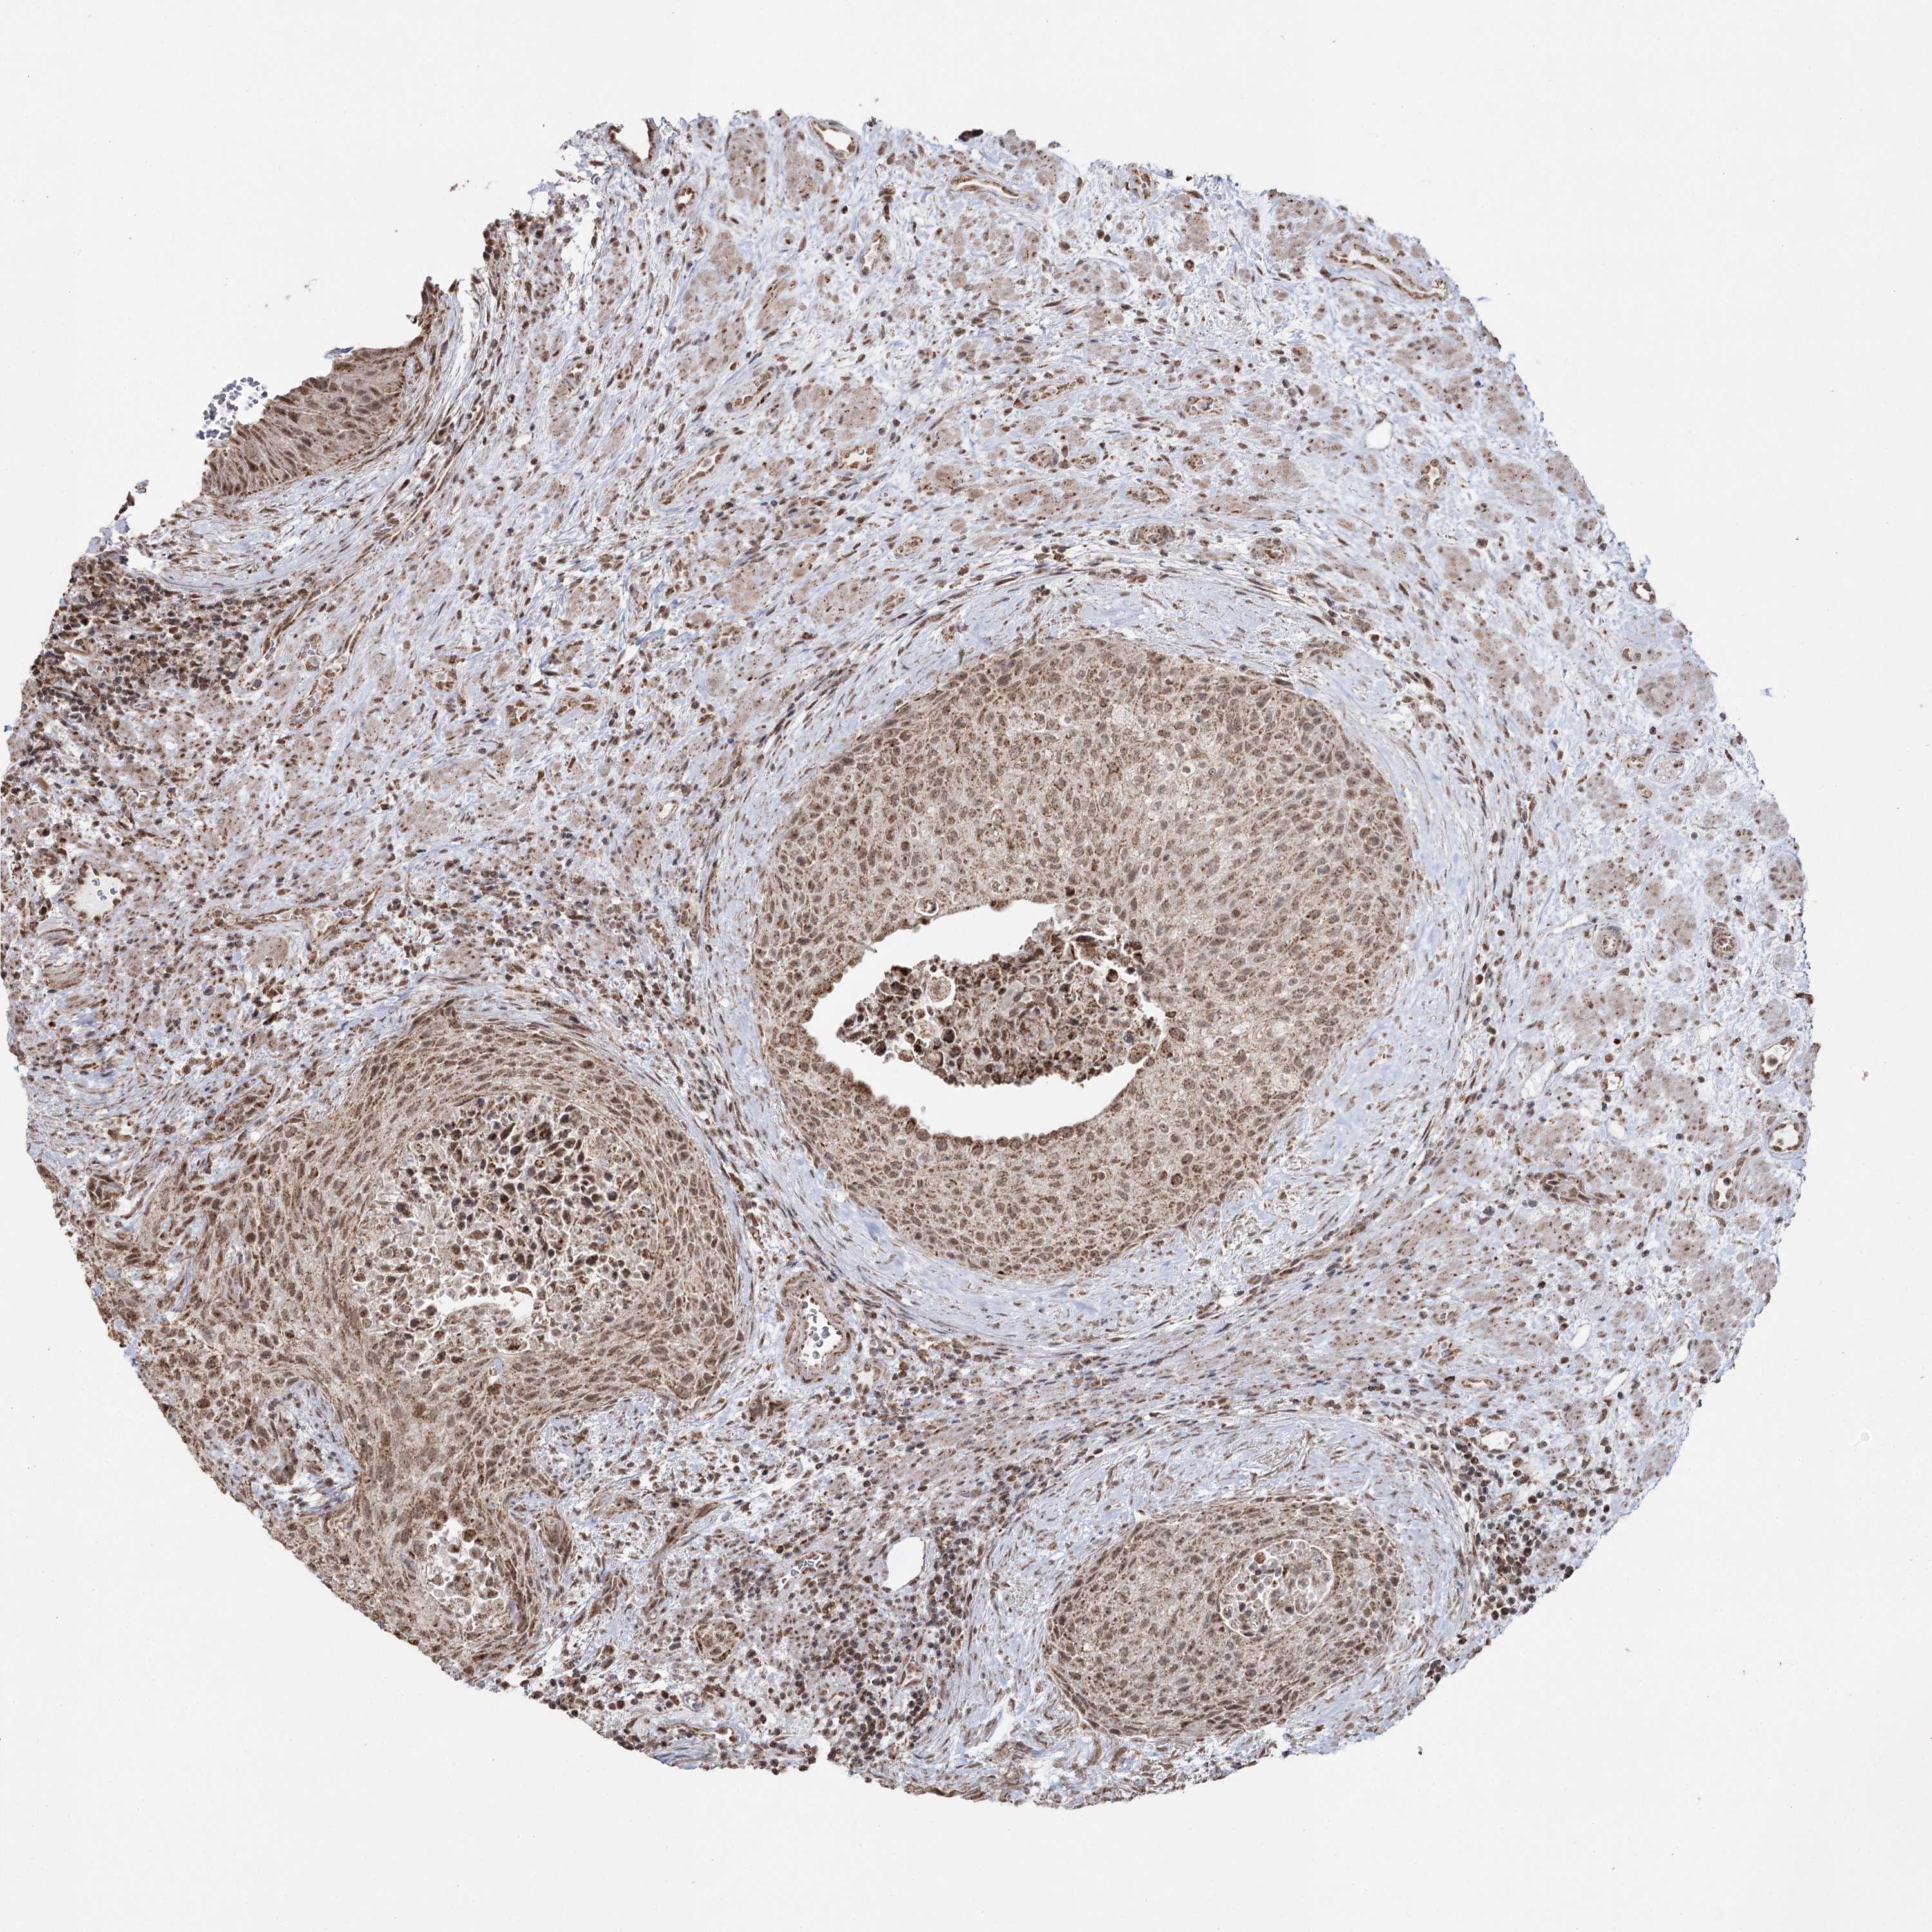

UROTHELIAL CANCER - Protein expressioni

A mouse-over function shows sample information and annotation data. Click on an image to view it in a full screen mode. Samples can be filtered based on level of antibody staining by selecting one or several of the following categories: high, medium, low and not detected. The assay and annotation is described here.

Antibody stainingi

Antibody staining in the annotated cell types in the current human tissue is reported as not detected, low, medium, or high, based on conventional immunohistochemistry profiling in selected tissues. This score is based on the combination of the staining intensity and fraction of stained cells.

Each image is clickable and will lead to virtual microscopy that enables deeper exploration of all samples and also displays staining intensity scores, fraction scores and subcellular localization as well as patient and tissue information for each sample.

Antibody HPA038484

Antibody HPA038485

Staining

High

Medium

Low

Not detected

Intensity

Strong

Moderate

Weak

Negative

Quantity

>75%

75%-25%

<25%

None

Location

Nuclear

Cytoplasmic/membranous

Cytoplasmic/membranous,nuclear

Urothelial carcinoma, High grade

Urothelial carcinoma, Low grade

Urothelial carcinoma, NOS